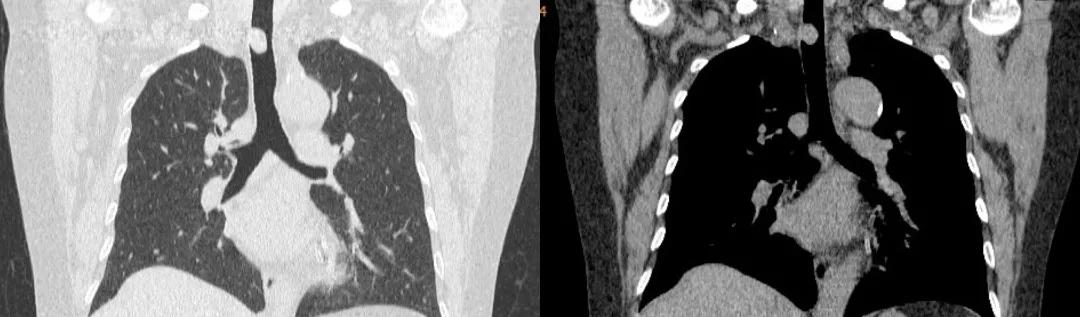

胸部CT:

胸部CT(冠状位)

四、影像学检查:表现为气管腔内的软组织密度肿块